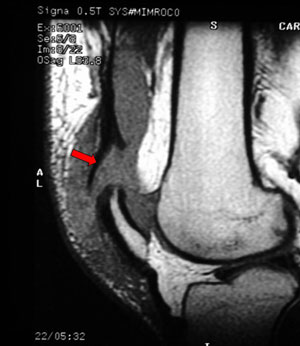

Deslocamento Patelar + Lesão do Retináculo

![]() |